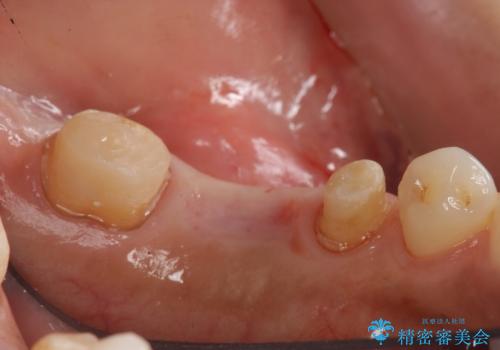

左下6番は残根状態だったため、やむなく抜歯を行い、⑤6⑦ブリッジとしました。

歯周外科手術を併用し、骨の高さを調整して歯の高さをしっかり出す手術(クラウンレングスニング)も行いました。

左下7番(一番奥)の歯の根管治療は横浜桜木町歯科院長大元が担当しています。

左下5番の根管治療は井上が担当しました。